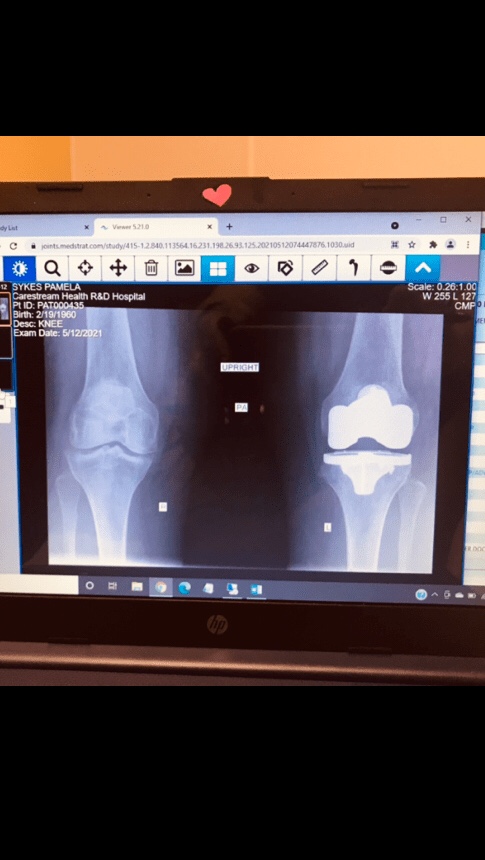

Illness update